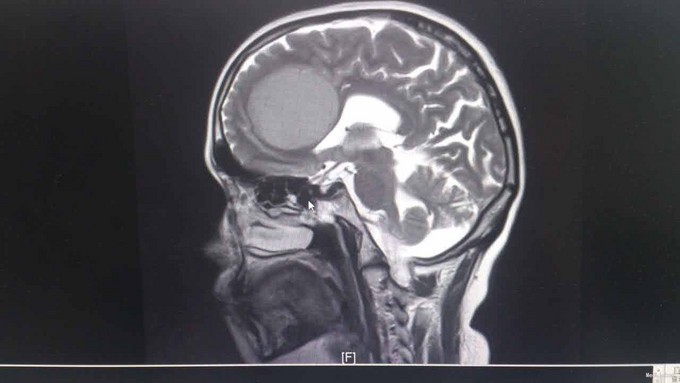

T:37℃,R: 20次/分,P:84次/分,BP:122/88mmHg。发育正常,营养中等,自主体位,步态平稳,表情自如,神志清楚,对答切题,查体合作。皮肤粘膜未见苍白、黄染,未见皮疹,无皮下出血点,无伤口。全身浅表淋巴结未扪及肿大。头颅无畸形。眉毛无脱落,眼睑无水肿、下垂、倒睫,睑结膜无苍白、充血,球结膜无充血、水肿,巩膜无黄染,角膜透明,眼球活动灵活,无凸出、凹陷、震颤、运动障碍,双侧瞳孔等大等圆,直径约3mm,对光反射灵敏,集合反射正常,左眼不能正常闭合。耳廓正常,无畸形,鼻部外形无异常,口唇红润,口腔粘膜未见出血点及溃疡,伸舌左偏,咽部无充血,扁桃体无肿大。颈软,无抵抗,颈静脉无充盈,肝颈静脉回流征(-),气管居中,甲状腺不大。胸廓对称无畸形、无局部膨隆或凹陷。呼吸平稳,节律规则。双侧呼吸动度对称。双肺部叩诊清音。双肺呼吸音清,未闻及干湿性啰音。心界不大,心率84次/分,律齐,各瓣膜区未闻及病理性杂音。腹平软,未及压痛,未及反跳痛,腹部未扪及包块,肝右肋下、剑突下未及,脾未触及,胆囊未触及,Murphy征(-)。移动性浊音阴性,肠鸣音正常,约4次/分。脊柱四肢无异常。生理反射存在,病理反射未引出。 专科检查:计算力、定向力、记忆力正常,双侧瞳孔等大等圆,直径约 4mm,对光反射灵敏,辐辏反射正常,眼球运动无受限,左侧眼睛不能正常闭合,左侧额纹消失,左侧鼻唇沟变浅,伸舌左偏,鼓腮无漏气,双上肢肌力5级,双下肢肌力5级,生理反射存在,病理反射未引出。 相关检查:血常规、大便常规、肝功能、凝血四项、离子四项、心肌酶、血脂四项、肾功能、肿瘤二项未见明显异常。 头颅增强MR1.左侧额叶大脑镰旁见团块状异常信号影,考虑脑膜瘤;2.双侧辐射冠区缺血灶;3.轻度脑萎缩。 肝胆脾胰B超、泌尿系B超未见异常。胸片示:1.双肺纹理稍增多、增粗,请结合临床;2.右上纵隔增宽,建议必要时CT检查。

诊断:脑膜瘤 治疗:甘露醇、地塞米松降颅压,择期手术治疗。